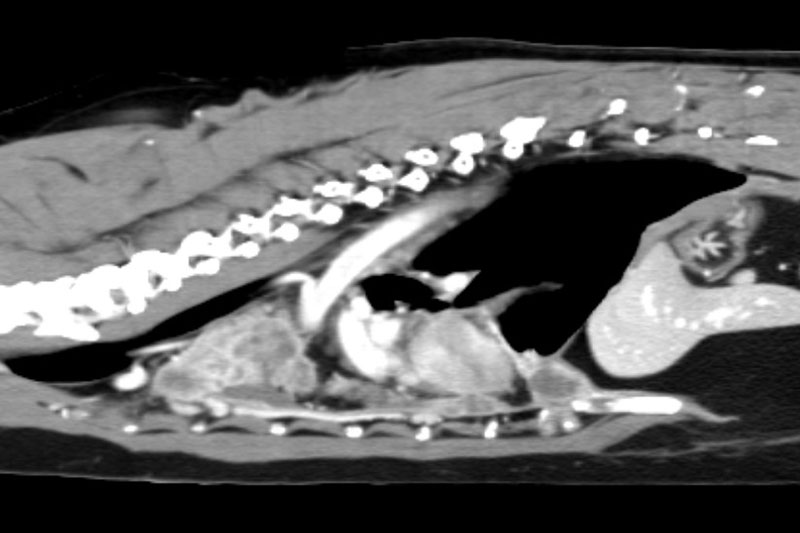

| 척추/관절 | 디스크 질환, 척추 골절, 관절염, 관절 기형 등 |

디스크(IVDD)와 척수 압박 병변의 정확한 위치 파악